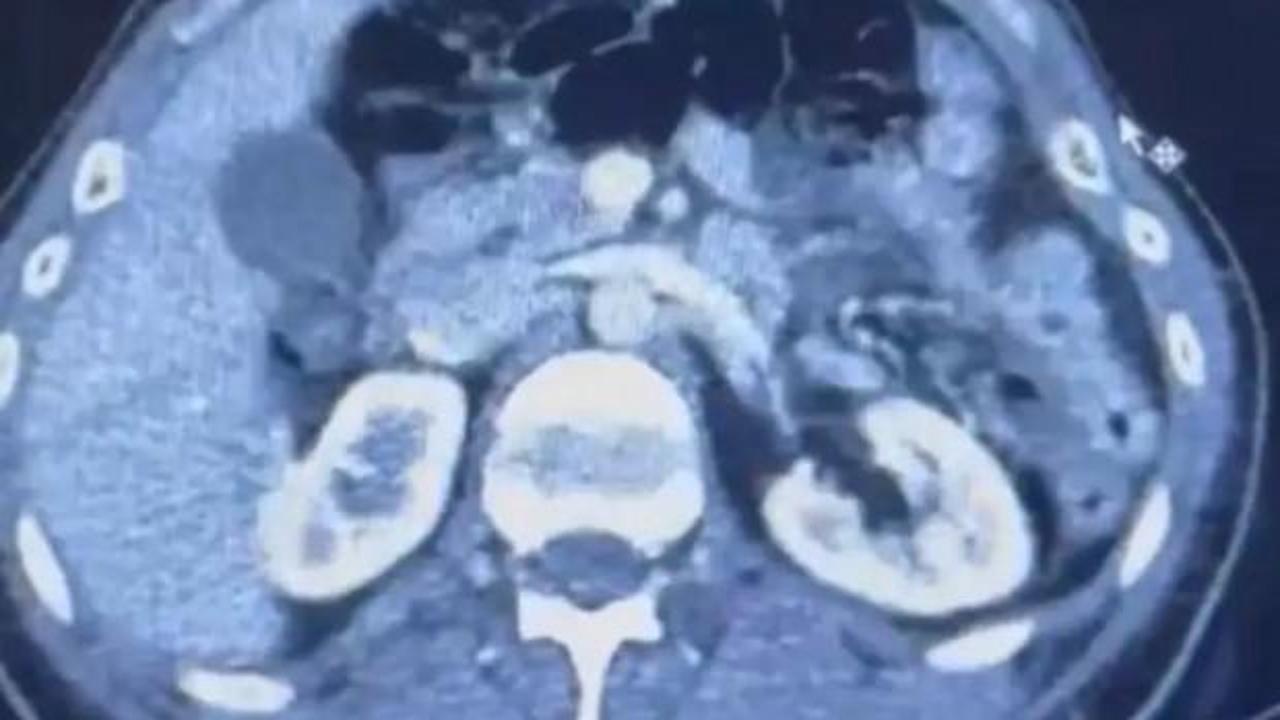

RÖNTGEN ÇEKİLDİ, KAPSÜLLER ORTAYA ÇIKTI

Şüphelilerden S.C. ve R.B.C. muayene edilmek üzere Kayseri Şehir Hastanesi'ne getirildi.

Röntgeni ve ultrason çekilen şüphelilerin midesinde yaklaşık 50 kapsülde 554 gram uyuşturucu olduğu tespit edildi.